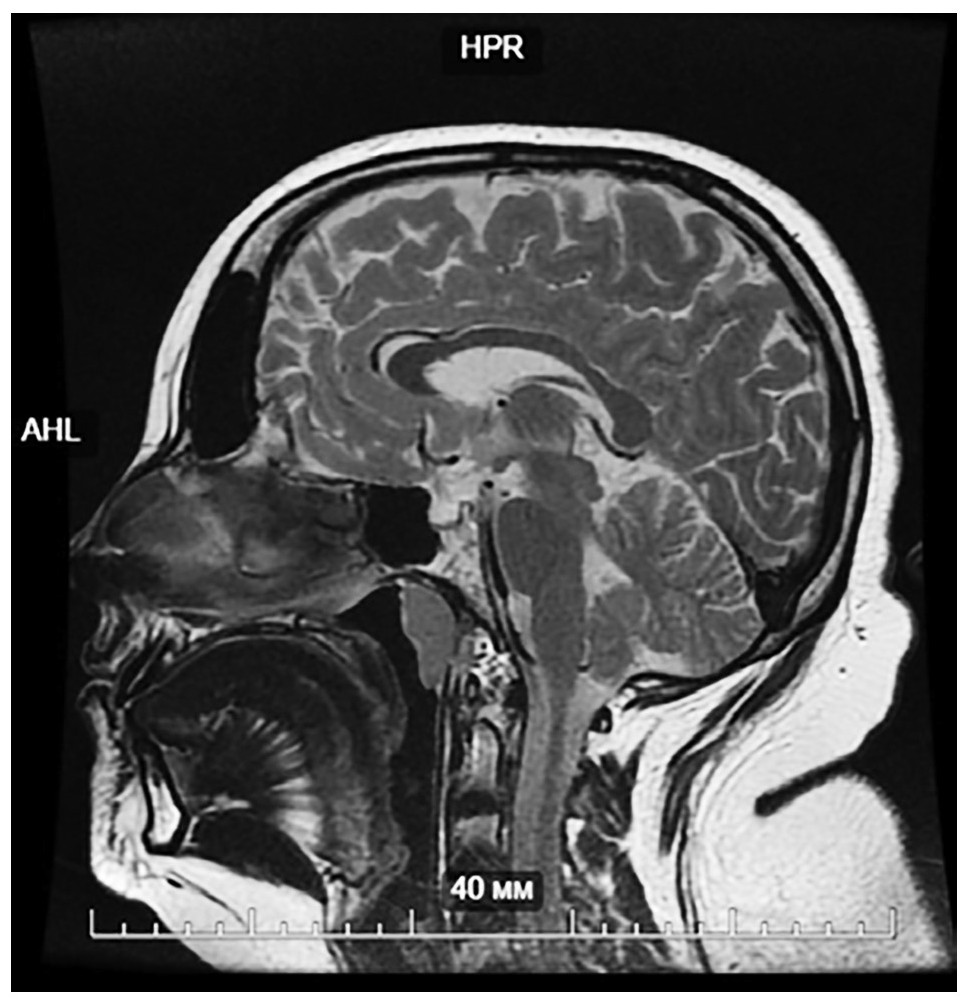

Пациентке была выполнена МРТ гипофиза с контрастированием (напряженность магнитного поля – 3Т): вертикальный размер гипофиза 2 см – «пустое» турецкое седло; аденомы гипофиза не выявлено (рис. 1).

Рис. 1. МРТ гипоталамо-гипофизарной области с контрастированием, Т2-взвешенное изображение, сагиттальная проекция. Вещество аденогипофиза располагается в виде тонкой полоски равномерной толщины вдоль дна турецкого седла, верхний контур железы ровный, вогнутый. Вещество гипофиза достигает максимальной толщины 2,4 мм. Воронка гипофиза определяется в сагиттальной плоскости. Хиазма определяется, не деформированна. Супраселлярная цистерна выраженно расширена, пролабирует в полость турецкого седла.

Fig. 1. Magnetic resonance imaging of the hypothalamic-pituitary region with contrast, T2-weighted image, sagittal projection. The substance of the adenohypophysis is located in the form of a thin strip of uniform thickness along the bottom of the sella turcica, the upper contour of the gland is smooth, concave. The substance of the pituitary gland reaches a maximum thickness of 2.4 mm. The pituitary infundibulum is determined in the sagittal plane. The chiasm is determined, not deformed. The suprasellar cistern is significantly expanded, prolapses into the cavity of the sella turcica.